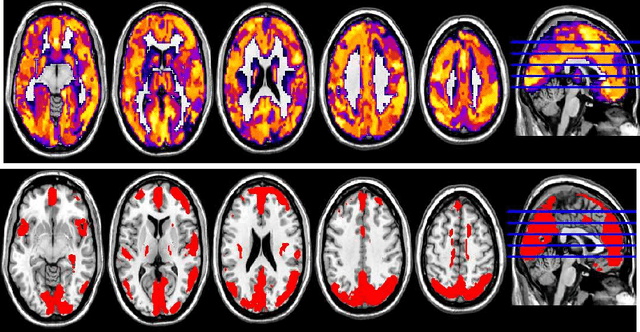

Abstract:In this paper, we focus on how to locate the relevant or discriminative brain regions related with external stimulus or certain mental decease, which is also called support identification, based on the neuroimaging data. The main difficulty lies in the extremely high dimensional voxel space and relatively few training samples, easily resulting in an unstable brain region discovery (or called feature selection in context of pattern recognition). When the training samples are from different centers and have betweencenter variations, it will be even harder to obtain a reliable and consistent result. Corresponding, we revisit our recently proposed algorithm based on stability selection and structural sparsity. It is applied to the multi-center MRI data analysis for the first time. A consistent and stable result is achieved across different centers despite the between-center data variation while many other state-of-the-art methods such as two sample t-test fail. Moreover, we have empirically showed that the performance of this algorithm is robust and insensitive to several of its key parameters. In addition, the support identification results on both functional MRI and structural MRI are interpretable and can be the potential biomarkers.